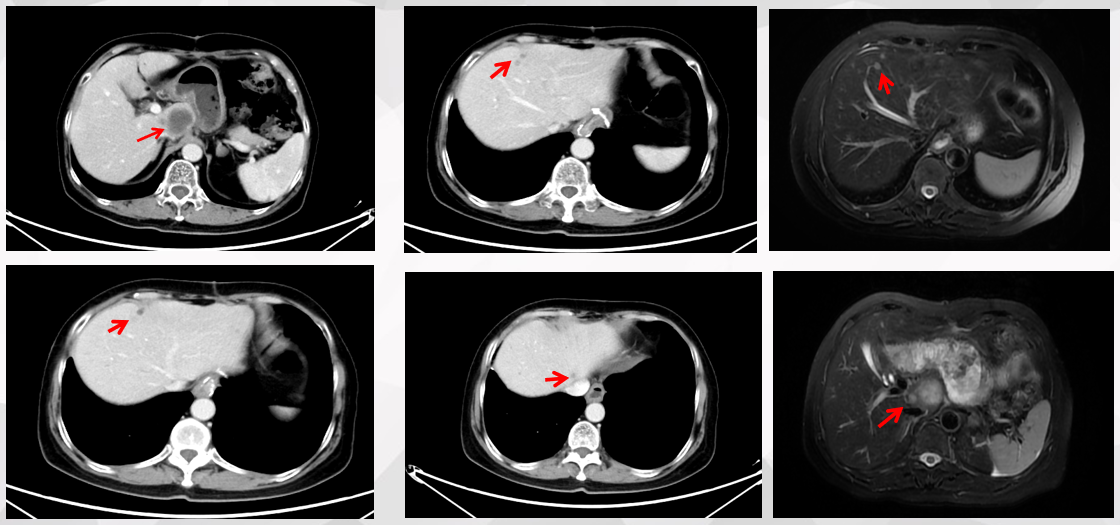

腹部CT (2023.3.14):肝内见数个结节状,最大一个位于尾状叶,直径约30mm(图1)。

腹部MR (2023.3.27):肝S1、2、3段见多发散在分布的类圆形病灶,大小不等,较大者位于肝S1段,最大截面约3.4cm*3.3cm,考虑转移。